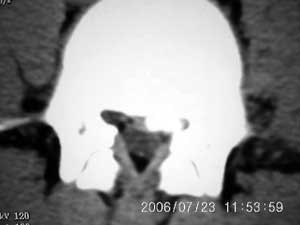

以下是引用xiaoniu在2006-7-23 12:47:00的发言:[br]椎体后缘软骨结节[br]【发病机制】尚未完全清楚,存在多种学说。一般认为青少年时期,脊柱负重压力及髓核膨胀性压力下,椎间盘组织通过椎体薄弱区疝入椎体内,局部骨小梁吸收被椎间盘组织代替形成软骨结节,周围骨小梁出现反应性硬化,逐渐形成骨壳包绕软骨结节。 椎体后缘软骨结节是椎间盘组织向后疝入椎体后缘的结果,为边缘性软骨结节的一种特殊类型。[br]【ct表现】椎体后缘类圆形、多囊状或不规则形的骨质缺损区,大小不一,位于椎体后缘正中或偏侧,其ct值等同于同层面的椎间盘,70~90hu,边界清楚,常有薄厚不一的硬化带。缺损区后方骨块突入椎管内,椎管狭窄,硬膜囊受压。[br]【鉴别诊断】本病诊断不难,需与以下疾病鉴别[br] 1 椎间盘突出钙化。2 后纵韧带骨化。3退变形成的骨赘。4锥体后缘撕裂性骨折。[br]上述疾病骨块影的形态及位置均各具特征,且椎体后缘均无低密度的骨结软节,鉴别不难。[br][br][本贴已被 xiaoniu 于 2006-7-23 12:52:32 修改过]